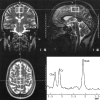

Background and purpose: Chronic alcohol abuse may cause neuropsychological disorders and result in brain atrophy. The purpose of this study was to evaluate the metabolic, morphologic, and functional cerebral changes in the early stage of abstinence from chronic alcoholism.

Methods: Seventeen alcohol-dependent patients underwent MR imaging and MR spectroscopy on days 1 through 3 and days 36 through 39 of abstinence. In addition, psychological performance measures testing intelligence, concentration, attention, and memory were applied. Neuropsychological data were correlated with spectroscopic and volumetric results by using a Pearson's product moment correlation. The same measurements were also performed in 12 healthy, age-matched control subjects. Peak integral values for N-acetylaspartate (NAA) and choline (Cho) were referred to the peak integral value of creatine (Cr) as the internal reference.

Results: NAA/Cr was decreased in the patients in both the frontal lobes and cerebellum immediately after cessation of drinking (days 1 through 3). After 36 to 39 days of abstinence, NAA/Cr had significantly increased in the patients and corresponded to performance on psychological tests. The Cho/Cr ratio was decreased in the cerebellum during early abstinence but was recovered on days 36 through 39. The patients had enlarged CSF spaces 1 to 3 days after detoxification, which decreased during sobriety. The extent of brain atrophy did not correspond to performance on psychological performance tests.

Conclusion: Regression of brain atrophy and metabolic recovery occurs at an early stage after abstinence from chronic alcohol abuse. MR spectroscopy findings return to normal metabolic levels within weeks after detoxification. The recovery of NAA/Cr is associated with improved performance on neuropsychological tests.